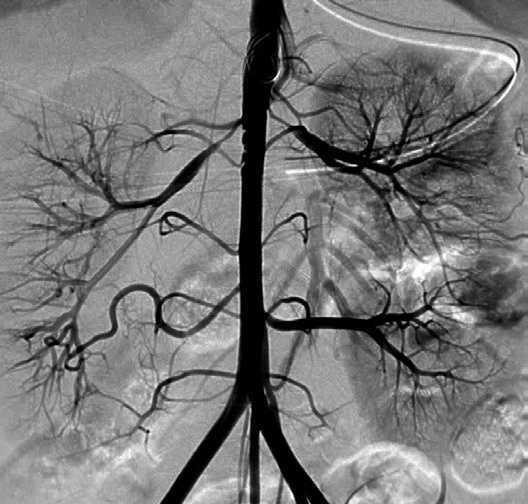

Arteriografía con contraste: estenosis tubular de aorta pararrenal con paredes delgadas, estenosis grave bilateral de las arterias renales principales de ambos riñones que además presentan una arteria renal polar accesoria de calibre normal (fig. 3).

Figura 3. Arteriografía aortorrenal: estenosis tubular de aorta pararrenal con paredes delgadas, estenosis grave bilateral de las arterias renales principales de ambos riñones que además presentan una arteria renal polar accesoria de calibre normal.